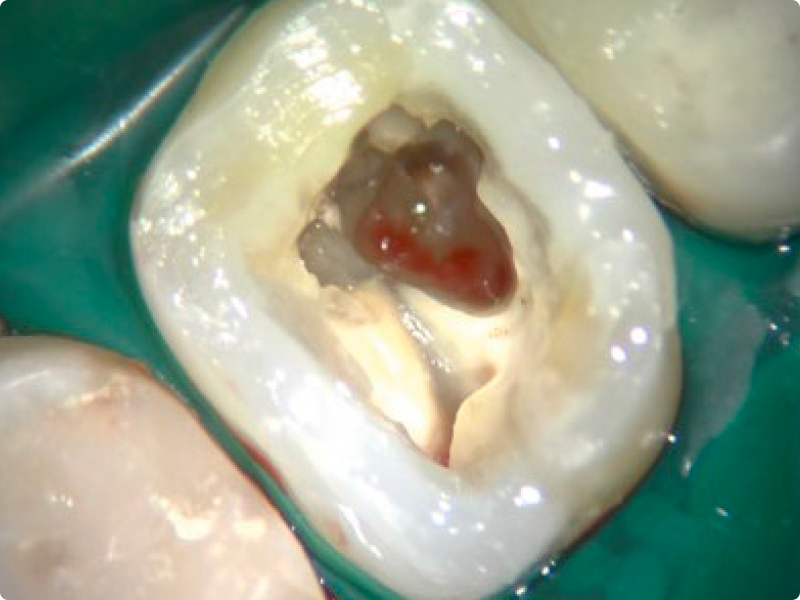

• Shaping calcified, curved and complex canals in primary treatments

• Mechanical shaping of the canal body in continuous rotation and reciprocation, with apical finishing on extracted teeth with pre-prepared access cavities (preferably with curved canals)

• Altered anatomies and iatrogenic damage: operative protocols for managing root resorptions, perforations and large apical openings